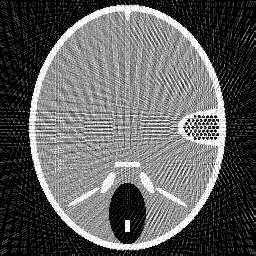

Figure 2. Results of different methods for reconstructing the head phantom with underdetermined rate 25% and relative noise level 0.2. (a) FBP (SNR=0.3253), (b) Landweber (SNR=0.1718), (c) Kaczmarz (SNR=0.1406), (d) L2-TV with scalar λ𝜆\lambda (SNR=0.0644), (e) Our method (SNR=0.0525), (f) λ𝜆\lambda in our method.

In Figure 2 and 3, we give the reconstruction results, which are shown in the same intensity range as the original phantom, from the simulated measurements with the noise level 0.2 and 0.8, respectively. Since the FBP algorithm is according to the analytical formulation of the inverse X-ray transform, it implicitly requires to have continuously measured clean data from the whole 0 to π𝜋\pi angular range. Therefore, it is not suited for reconstructing from noisy limited data. We can clearly see many stripe artifacts due to the noise and sparse projection angles in the FBP results. Both the Landweber and Kaczmarz’s methods perform better than FBP, but there are still some visible artifacts in the reconstruction. By using the TV regularization in the L2-TV and our methods, we potentially assume that the reconstructions are piecewise constant, which evidently reduces the influence of the noise and avoids stripe artifacts. In addition, comparing the results from the L2-TV and our methods, we find that our method suppresses artifacts much better while reconstructing most details. For instance, the grey region in the head and the black dotted region on the right side. With respect to SNR, it is also clear that our method gives the best reconstruction results. In Figure 2 (f) and Figure 3(f), we also plot the λ𝜆\lambda function obtained by our method. One can see that in the more textured regions λ𝜆\lambda is large in order to preserve the details, and in the more homogenous regions it is small to reduce artifacts.